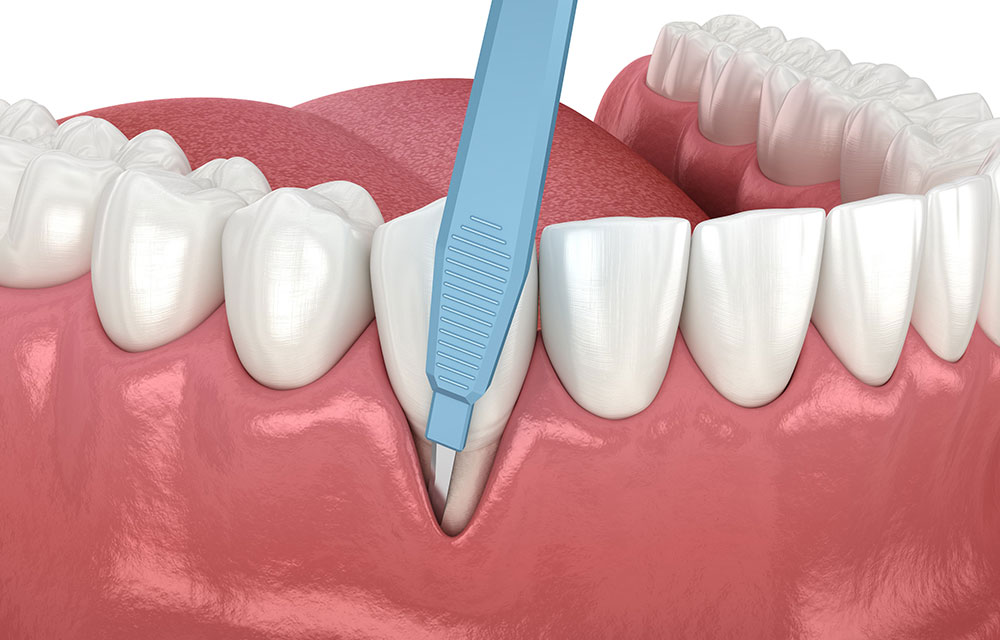

歯肉切除手術

メスを使って歯周ポケットを除去し、健康な歯肉組織を回復させます。